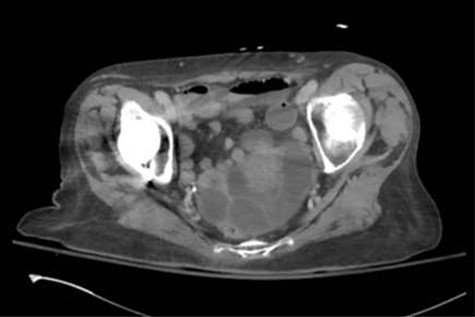

On physical exam, she was afebrile and normotensive. Her abdomen was soft with tenderness to palpation in the suprapubic region. Laboratory data demonstrated a white blood count of 7,200, a hemoglobin of 13.2, and a hematocrit of 39.3 percent. Renal function, electrolytes, liver function, and urinalysis were all within normal ranges. A CT of the abdomen and pelvis with intravenous contrast was obtained and revealed distended fluid-filled loops of small bowel mostly within the pelvis. There was evidence of some wall thickening and perienteric fat stranding. A transition point was felt to be within the pelvis (Figs 1 and 2).

Axial slice of the CT of the abdomen/pelvis demonstrating distended fluid-filled loops of small bowel mostly within the pelvis. There was evidence of some bowel wall thickening and perienteric fat stranding.